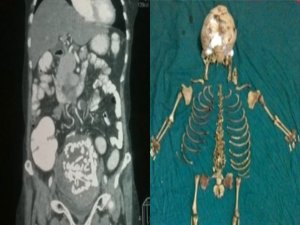

ANNE KARNINDAN 36 YILLIK BEBEK İSKELETİ ÇIKTI